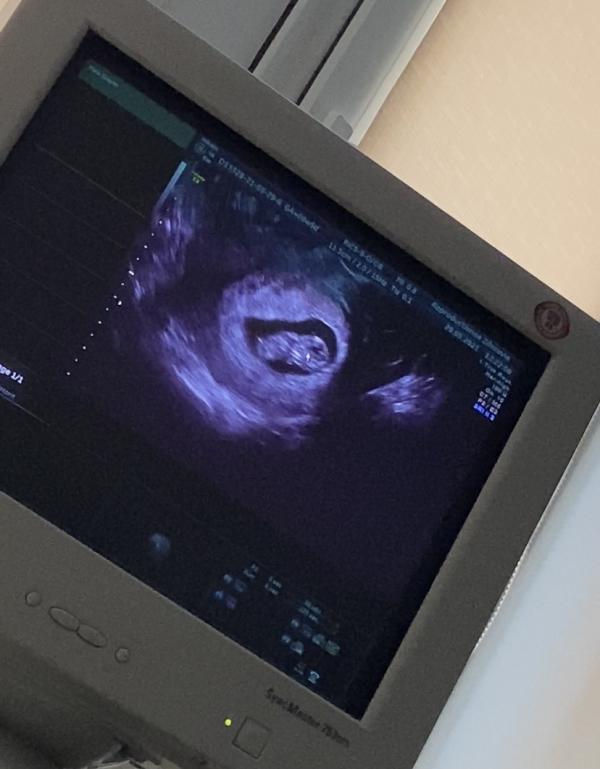

Нам 9 нед и 5 дней🙌🏼и я опять ходила сегодня на узи😻да неугомонная ,да переживаю ...я хочу все знать😁я та самая мама которая тревожная🙈

Это было 4 узи за все пока время . И там уже совсем совсем прям человечек💞мой долгожданный ребёночек❤️чсс 178❤️соответствует сроку 9 нед и 3 дня.время летит🤩через две недели уже скрининг а казалось вот вот только ждала хгч...